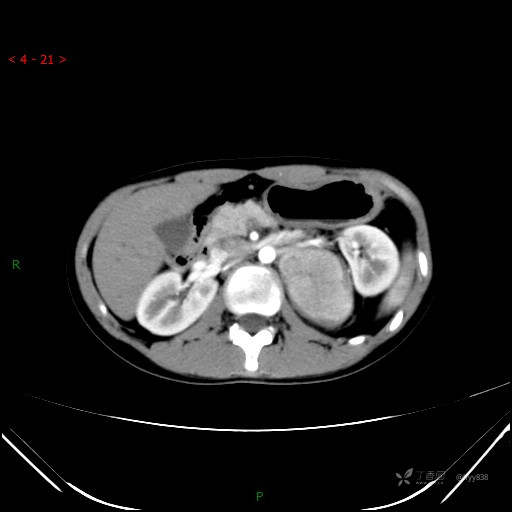

CT值